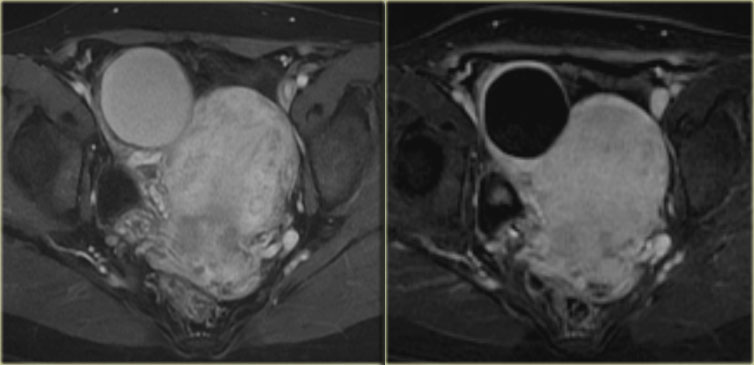

Endometrioid ovarian carcinoma

On ultrasound both ovaries are markedly enlarged and contain cystic components with intracystic solid components (arrows).

The complex solid-cystic lesions, in addition to being bilateral, are suspicious for a cystic ovarian neoplasm and warrant further evaluation.

Again, the role of imaging is to confirm a lesion is present and to decide that this is not a lesion that can be classified as definitely benign nor a lesion that can be safely followed-up: action is required.

CT of the same patient confirms large bilateral complex solid-cystic lesions, bulging into the abdomen.

The purpose of the CT is not to confirm what was already known from the ultrasound, but to stage disease.

On the basis of CT (or of MRI) it is not possible to determine the histologic type of the tumor.

This is not relevant. This patient will undergo surgery.

For epithelial tumors - by far the most common group of malignant ovarian tumors - even after surgery, the exact tumor subtype is much less important for the prognosis than factors such as FIGO-stage, tumor differentation grade, and how succesful surgery was in removing all of the disease.

For this patient the relevant findings are on the image on the left.

There is a peritoneal implant.

The tumor was resected and pathology showed this was an endometrioid ovarian carcinoma.